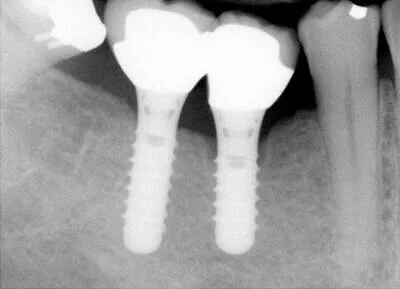

Aurora Periodental Centre does most of the implant surgery for Dr. Ehrlich’s patients, and you can visit their website for more information. In some simpler cases, Dr. Ehrlich places the implants right in this office. Dr. Ehrlich restores the teeth on the implants. Once the implants are in place, all the rest of the dentistry is just “nuts and bolts"- no drilling, noise or anaesthetic involved. (Photos below show the before, during, and after of 2 implants by x-ray, as well as photos of the temporary caps and the finished product!)

implant_xray_preop.jpg

Missing Teeth

Implants placed, waiting for bone to grow in.